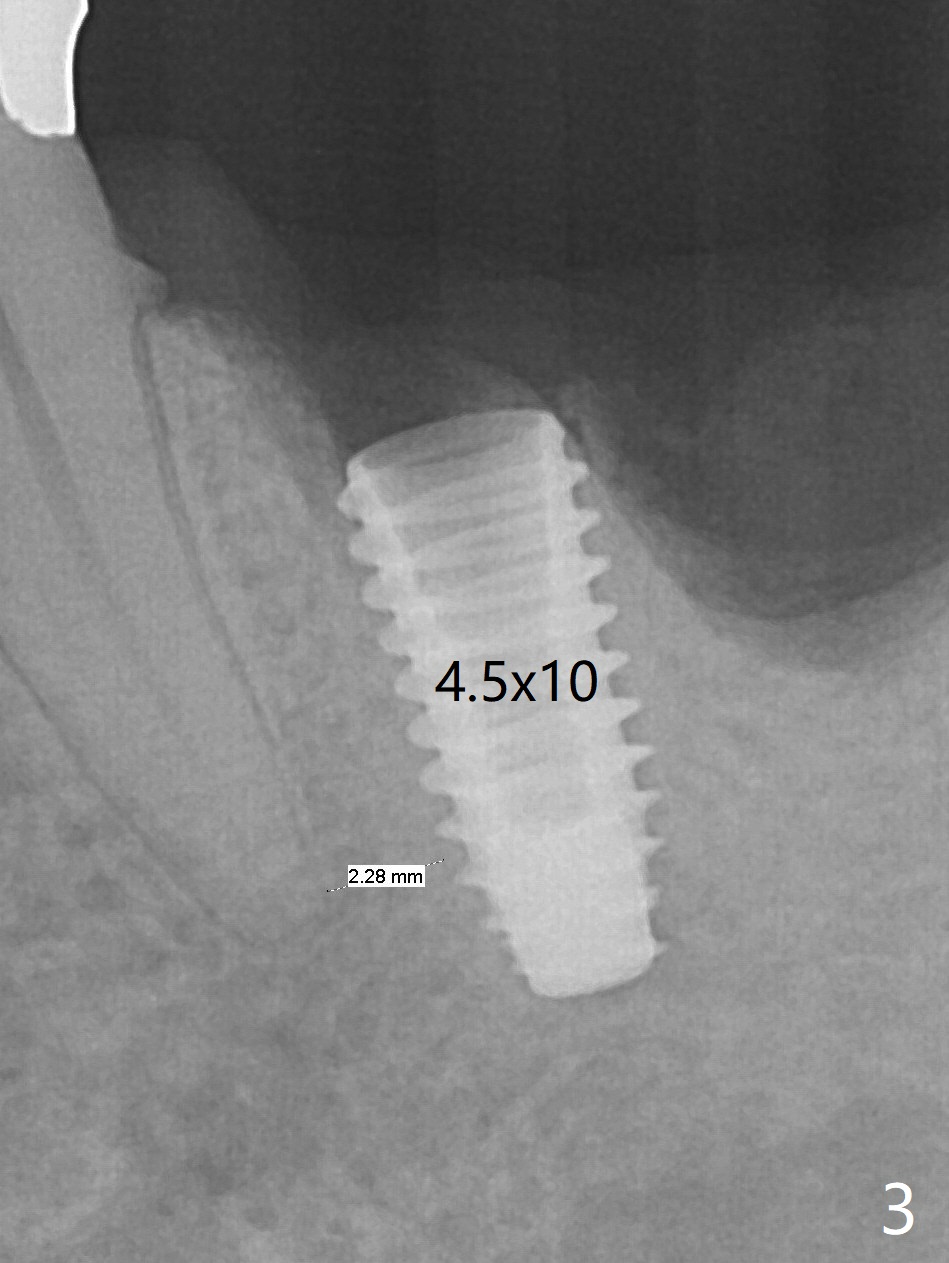

The guide does not arrive when the tooth #19 is extracted. Osteotomy is initiated free hand in the mesial socket as planned, slightly lingual, for 11.5 mm (Fig.1). Following sequential osteotomy, a 4.5x10 mm implant is placed subcrestal septally (Fig.2 S) and 2.3 mm from the neighboring apex (Fig.4). A 5.5x5(4) mm abutment is placed immediately and allograft is placed in the remaining sockets (Fig.4 *). An immediate provisional is fabricated to keep the graft in place (Fig.5 P; the most secure socket preservation).